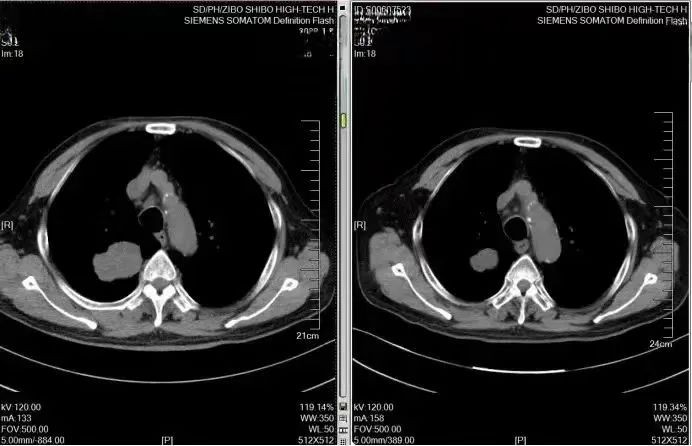

治疗前:右肺上叶后段见不规则团块状高密度灶,大小约5.3*3.8*4.4cm

1月5日:大小约5.3*3.8*4.4cm ;2月3日:大小约5.0*3.7*4.1cm ;

时隔一个月后,孙先生来院复查,身体不适症状明显缓解。孙先生定时返院复查,五个月后根据治疗前后影响对比结果发现,肿瘤病灶明显缩小,由原来的5.3*3.8*4.4cm缩小为2.5*2.6*2.8cm,治疗效果显著。

5个月后复查,病灶明显缩小,治疗前:大小约5.3*3.8*4.4cm 治疗后:大小2.5*2.6*2.8cm

治疗前(2023.1.5)VS治疗后(2023.6.15)